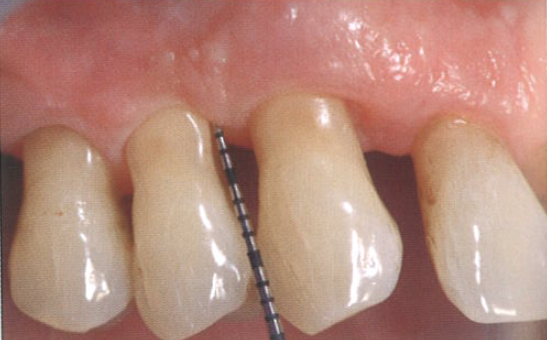

患者表示相比于手术治疗而言,更愿意进行激光辅助的非手术治疗(图9a)。

尖牙近中面的探诊深度大约为10 mm(图9b),相邻前磨牙近中面的探诊深度为7 mm。

图9  a为牙周激光辅助治疗;b为尖牙近中面的探诊深度深度,大约为10 mm